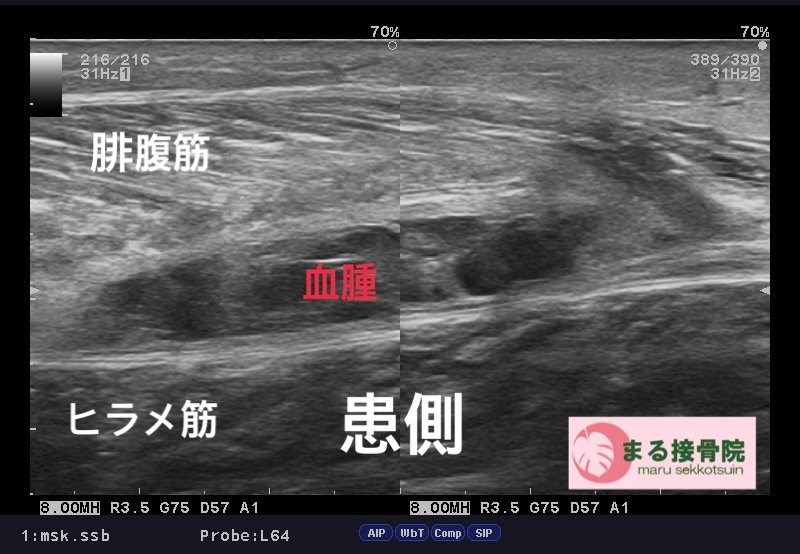

今日の患者様は、テニス中、ふくらはぎが「誰かに後ろから蹴られた、、、ような」「力を入れた時にブチッ!!と痛みがはしった、、、」と御来院。

肉離れはスポーツ中、日常生活で階段を駆け上がるなど、筋肉に急激な力が加わった時に、筋繊維が損傷した状態。

治療は、しっかり問診、触診、視診を行い、超音波画像診断装置で患部状態、深さ、広さをしっかり確認し、早期復帰、回復に向けて対処していきます。